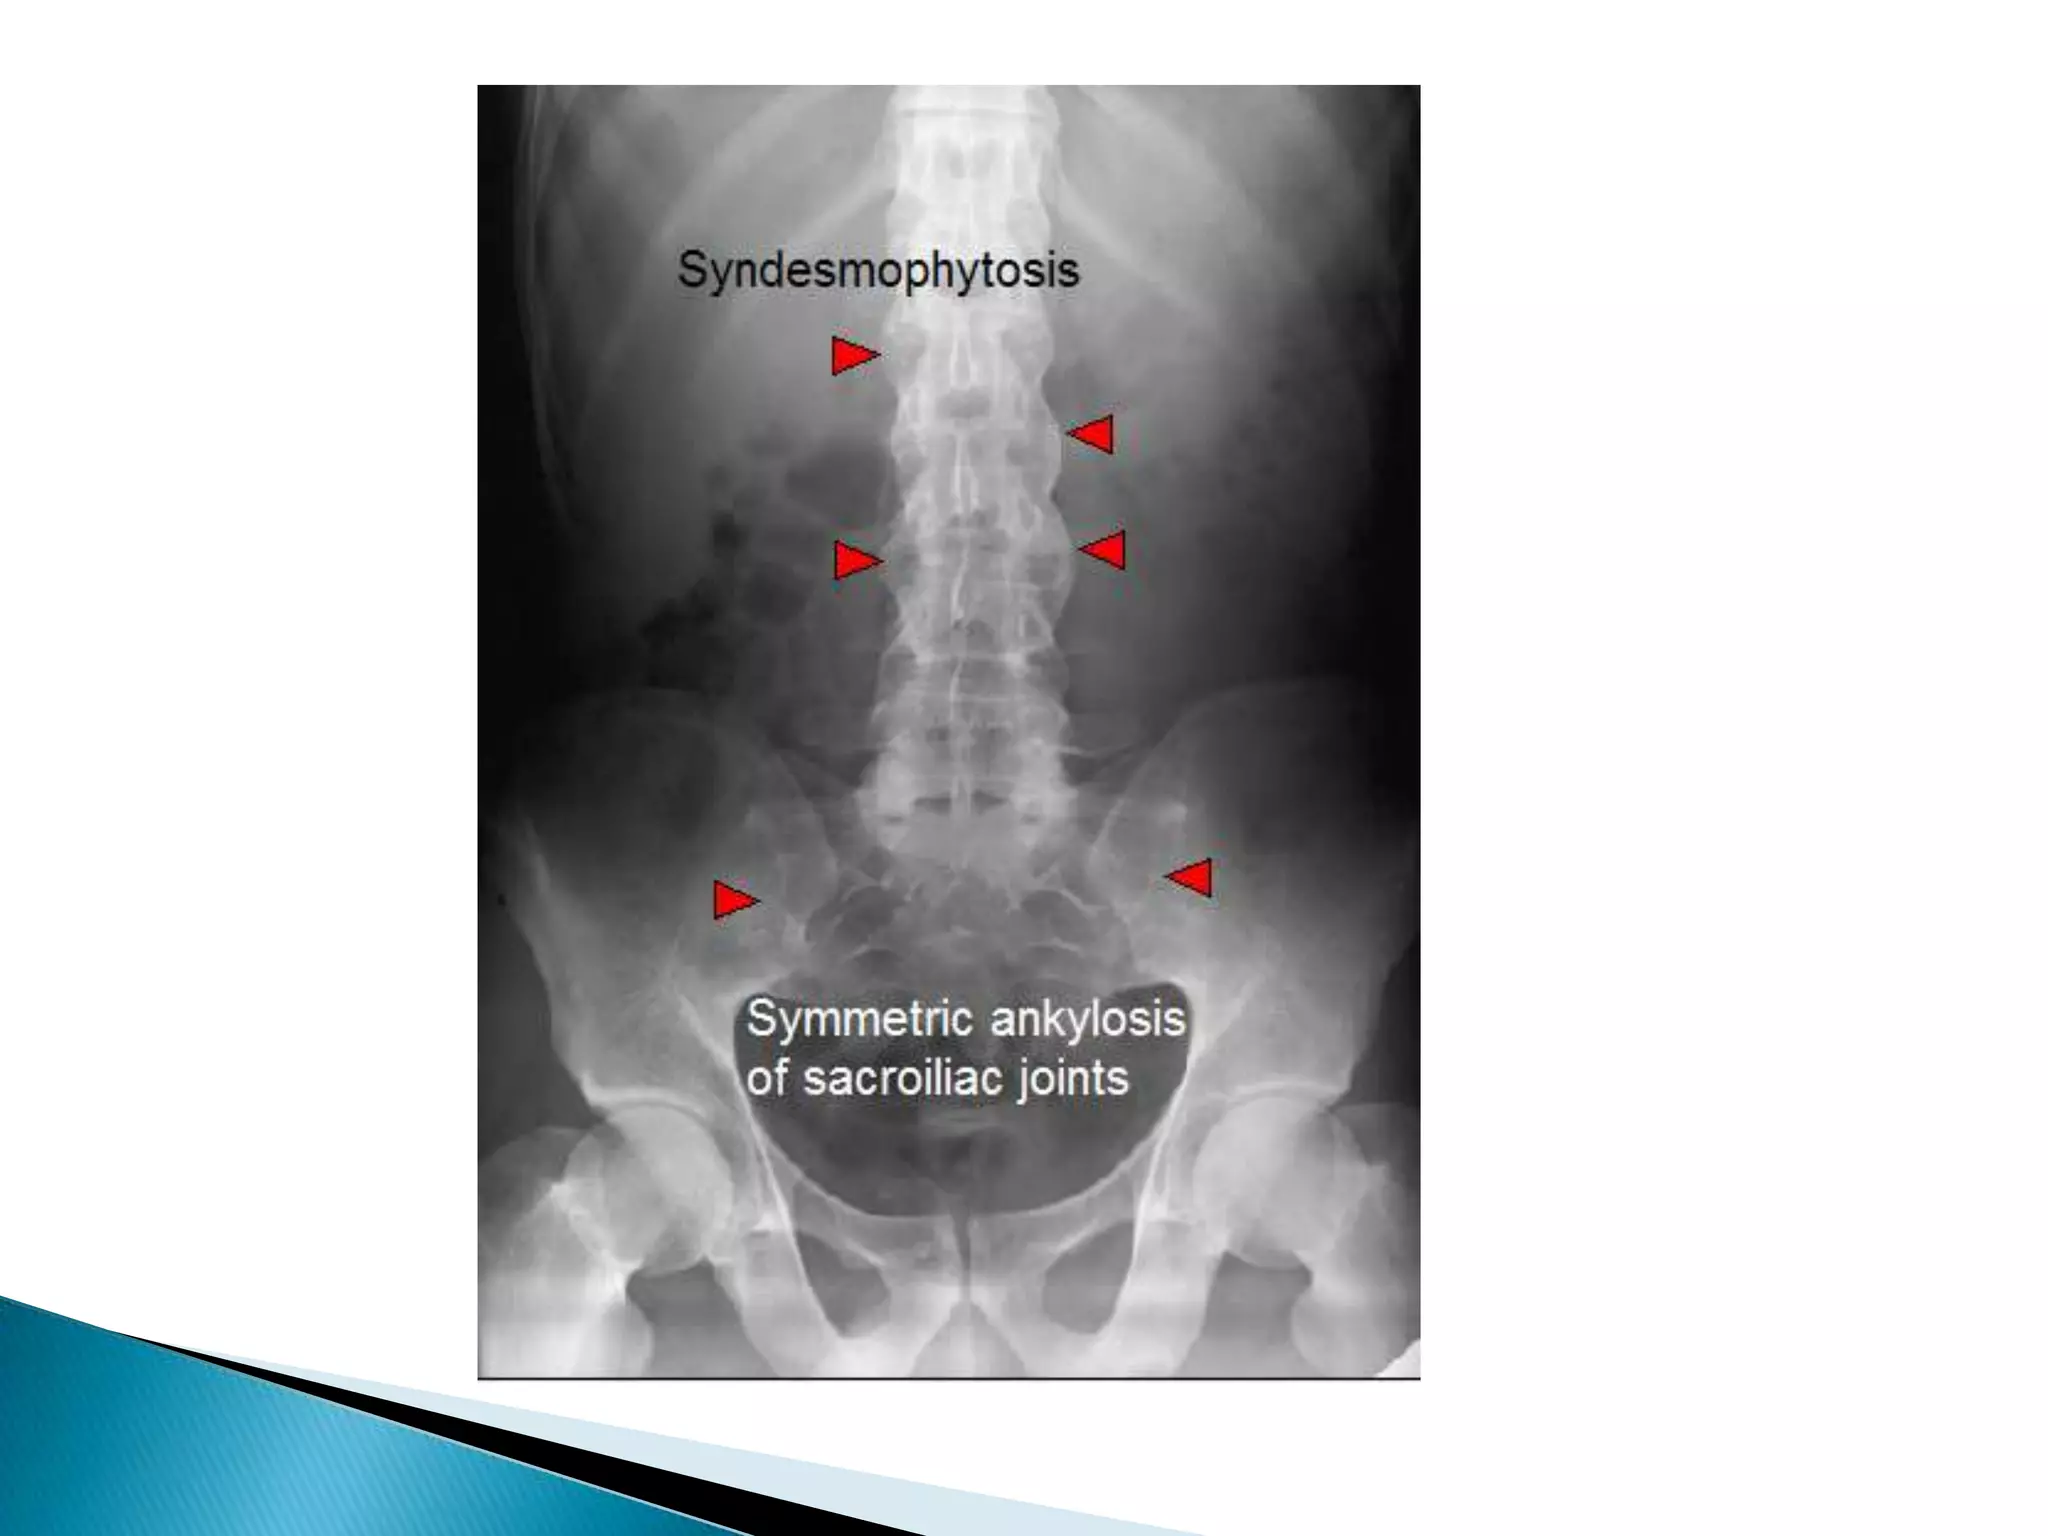

Radiological finding of ricketsThe changes are  maximal where bone growth is occur, so they best seen in the knees, wrists & anklesLoss of provisional zone of calcification.Indistinct metaphyses& metaphyses become irregular and cupped.Wide growth plate.decreased bone density.Deformities of the bones occur because of bone softening.Greenstick fractures are common

This patient shows abnormal bone density, with coarsened abnormal trabeculae in a generalized pattern.  Even more prominently, we see widened and irregular metaphysesRickets

Radiological finding ofricketsThe changes are maximal where bone growth is occur, so they best seen in the knees, wrists & anklesLoss of provisional zone of calcification.Indistinct metaphyses& metaphyses become irregular and cupped.Wide growth plate.decreased bone density.Deformities of the bones occur because of bone softening.Greenstick fractures are common

This patient showsabnormal bone density, with coarsened abnormal trabeculae in a generalized pattern. Even more prominently, we see widened and irregular metaphysesRickets